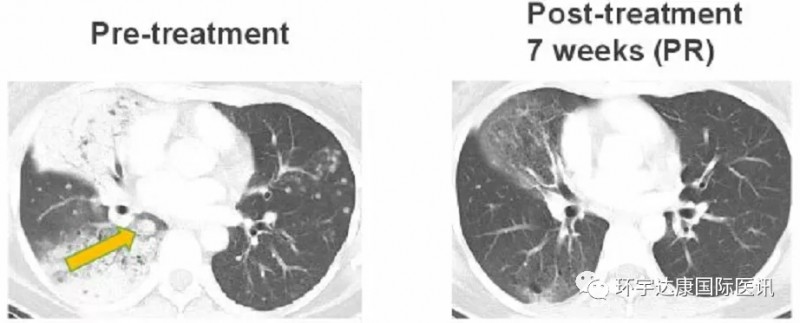

2、有效克服克唑替尼耐药

一位38岁的女士确诊为CD74-ROS1融合阳性非小细胞肺癌,之前接受过化疗和克唑替尼的治疗,但是出现了一种新的耐药突变ROS1 G2032,患者接受Taletrectinib(600mg,QD)治疗,在第7周时,肺部肿瘤迅速缩小,评效为部分缓解(PR),目前该患者仍在接受治疗中。